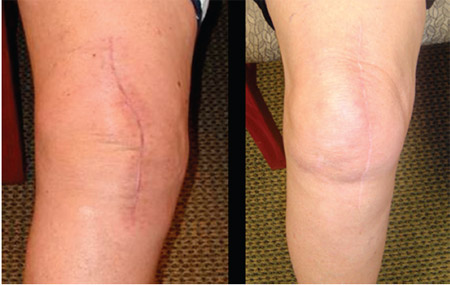

Pressure-film evaluation revealed the two distinct areas of stress in most knees, but some knees had no pressure points; this lack of pressure points appeared to be caused by fat distribution throughout the kneeling areas, particularly in obese patients who tended to have large fat deposits medially or a bulging intra-articular fat pad. In thin patients, the tibial tuberosity and the proximal crest of the tibia were consistently most prominent. As the patient or healthy volunteer leaned forward, distinct areas of pressure over the patella developed. When the total knee arthroplasty incision was located more medially (Fig. 8), most patients found little discomfort when kneeling one year after surgery.

fig 8

Fig. 8 Photographs showing healed medial midline incisions.